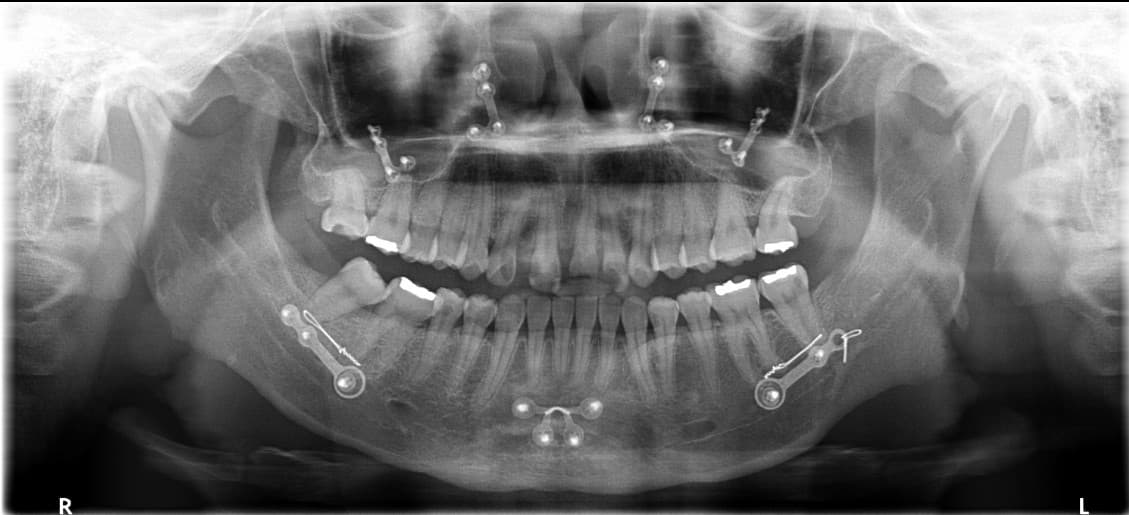

3D Digital Guide Surgery

Fast and comfortable surgery

Minimized swelling, pain, and bone grafting

1

3D Oral Scanning

Precise diagnosis through oral scanning

2

Virtual Surgery Design

Optimal placement planning on computer

3

Guide Placement

Precision guidance device with 1mm accuracy

4

Minimal Incision Surgery

Reduced procedure time, minimized pain/swelling

5

Simulated Surgery Verification

Minimized deviation for higher satisfaction

Digital Guided

Implant Before & After